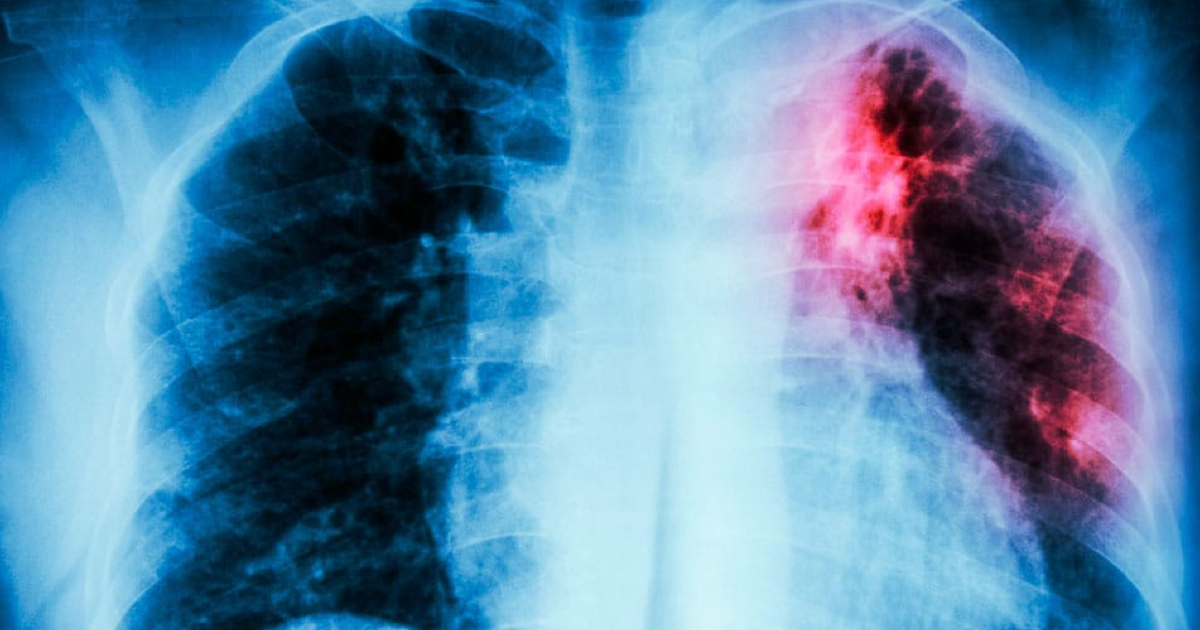

La tuberculosis se denomina tuberculosis entre los profesionales sanitarios. Esta enfermedad, que tiene un aspecto contagioso, es una enfermedad que...

Además de los síntomas de la enfermedad de tuberculosis, la atención al paciente con tuberculosis también es un tema interesante...

La tuberculosis es una enfermedad transmitida por el aire causada por una infección del tracto respiratorio que se instala en...